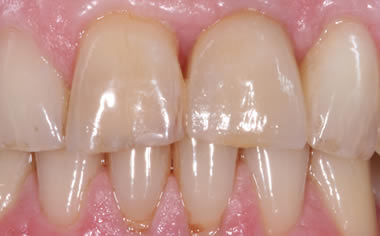

More front teeth replaced by dental implants

Case Three (4 images)